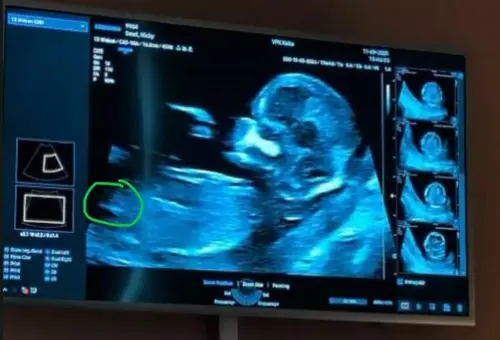

Hi allemaal, ik ben heel benieuwd.. ik denk dat dit wel een goede foto is van de NUB, toch? Wat zien jullie? Meisje of jongen?

Ik denk een meisje

Ik denk ook een meisje

Meisje